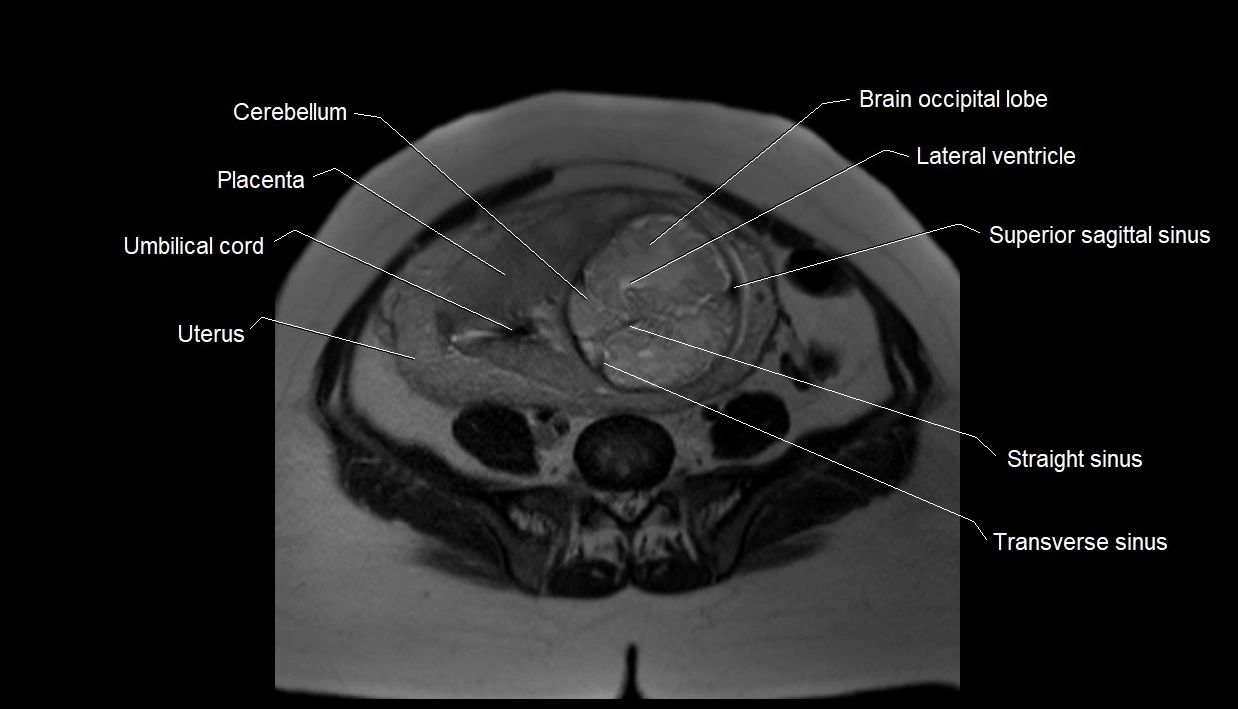

MRI Appearance

T2 HASTE (T2 GRE):

• Amniotic fluid shows very bright hyperintense signal

• Provides natural contrast against fetus and placenta

• Small particles (vernix) may appear as scattered hypointense foci within bright fluid

T1 GRE:

• Amniotic fluid shows low signal intensity (dark)

• Hemorrhage, infection, or proteinaceous content may cause focal or diffuse high signal intensity